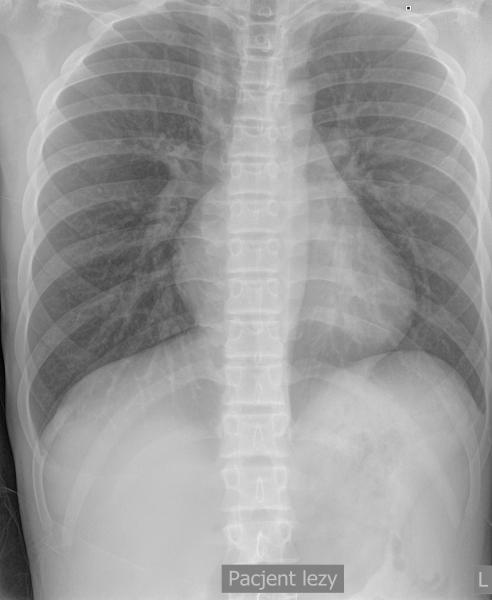

Przypadek 44: U 18-miesięcznego chłopca po operacji przepukliny przeponowej lewostronnej (operacja przeprowadzona po urodzeniu) wykonano kontrolne zdjęcie rtg klatki piersiowej.

Rozpoznanie: Na zdjęciu rtg klatki piersiowej, w okolicy nadprzeponowej po stronie lewej, rzutuje się owalna przestrzeń powietrzna - pętla jelitowa w klatce piersiowej? Podejrzenie nawrotu przepukliny.